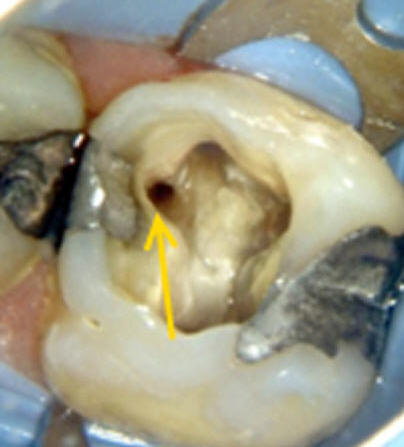

Primer molar superior Presenta tres raíces, las cuales se distribuyen dos vestibulares y una palatina. La raíz mesiovestibular es achatada en sentido mesiodistal y amplia en sentido vestibulopalatino.El conducto mesiovestibular con frecuencia es curvo y de sección en forma de hendidura. La existencia de dos conductos en esta raíz, puede presentar la siguiente configuración:

Estos conductos pueden unirse a distintos niveles, terminando en un foramen único o ser de trayectoria independiente hasta el ápice y terminar en forámenes separados. Son atrésicos y de difícil tratamiento en especial el palatino. La raíz distovestibular tiene dimensiones menores que la mesiovestibular y no presenta curvaturas acentuadas. El conducto distovestibular (Color verde) por lo general es atrésico y puede presentar curvaturas. La raíz palatina es la más voluminosa de forma cónica y sección circular. Puede ser recta o curva. Cuando es curva, el sentido e la curva es hacia vestibular. El conducto palatino (Color rojo) es amplio y de fácil acceso, rectilíneo o con una curva leve hacia vestibular. |